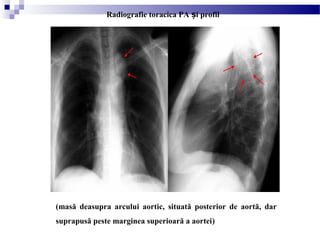

(masă deasupra arcului aortic, situată posterior de aortă, dar

suprapusă peste marginea superioară a aortei)

Radiografie toracica PA i profilș